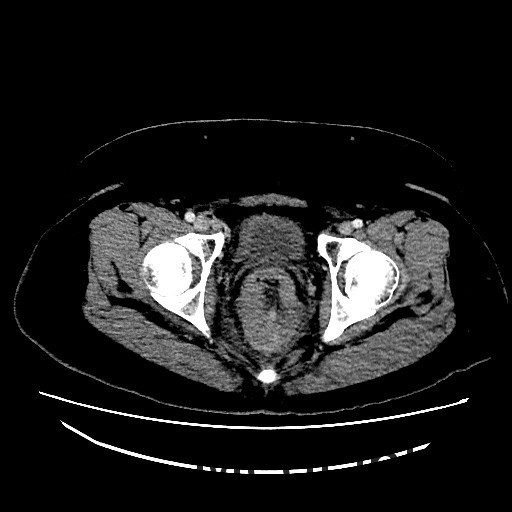

查体:肛查(KC位):肛周未见外痔,直肠指检可及环形多发内痔,部分质地较硬,有触痛,直肠壁可及多发结节,有触痛,指套退出有染血。 辅查:腹部CT示:直肠癌,累及肠壁全层,并周围肠系膜多发淋巴结转移,全身核素骨扫描结果提示:右侧坐骨轻度代谢活跃,建议定期复查以排除骨转移瘤可能,肿瘤标记物未见明显异常。肠镜示:1.直肠Ca?2.结肠息肉(已钳除)。

讨论:胃肠道是原发性结外淋巴瘤最常见的累及部位。其中胃是最常见的发病部位,其次是小肠,而结肠和直肠少见。本例属于直肠淋巴瘤,属于少见肿瘤,影像表现与直肠癌相似,因此临床常常误诊为直肠癌,本例即误诊为直肠癌。影像学上只要认真观察一般能通过以下几点将两者鉴别开:淋巴瘤一般累及的肠段较长,肠壁较厚,肠腔变窄不明显,呈动脉瘤样扩张,没有肠梗阻表现,周围脂肪界面清晰。而大肠癌则相对较局限,常伴有肠腔的狭窄及肠梗阻的表现,而且常通过浆膜直接向周围浸润,周围脂肪间隙模糊。只要认真寻找这些影像征象,还是能够将两者较好的区别开来。